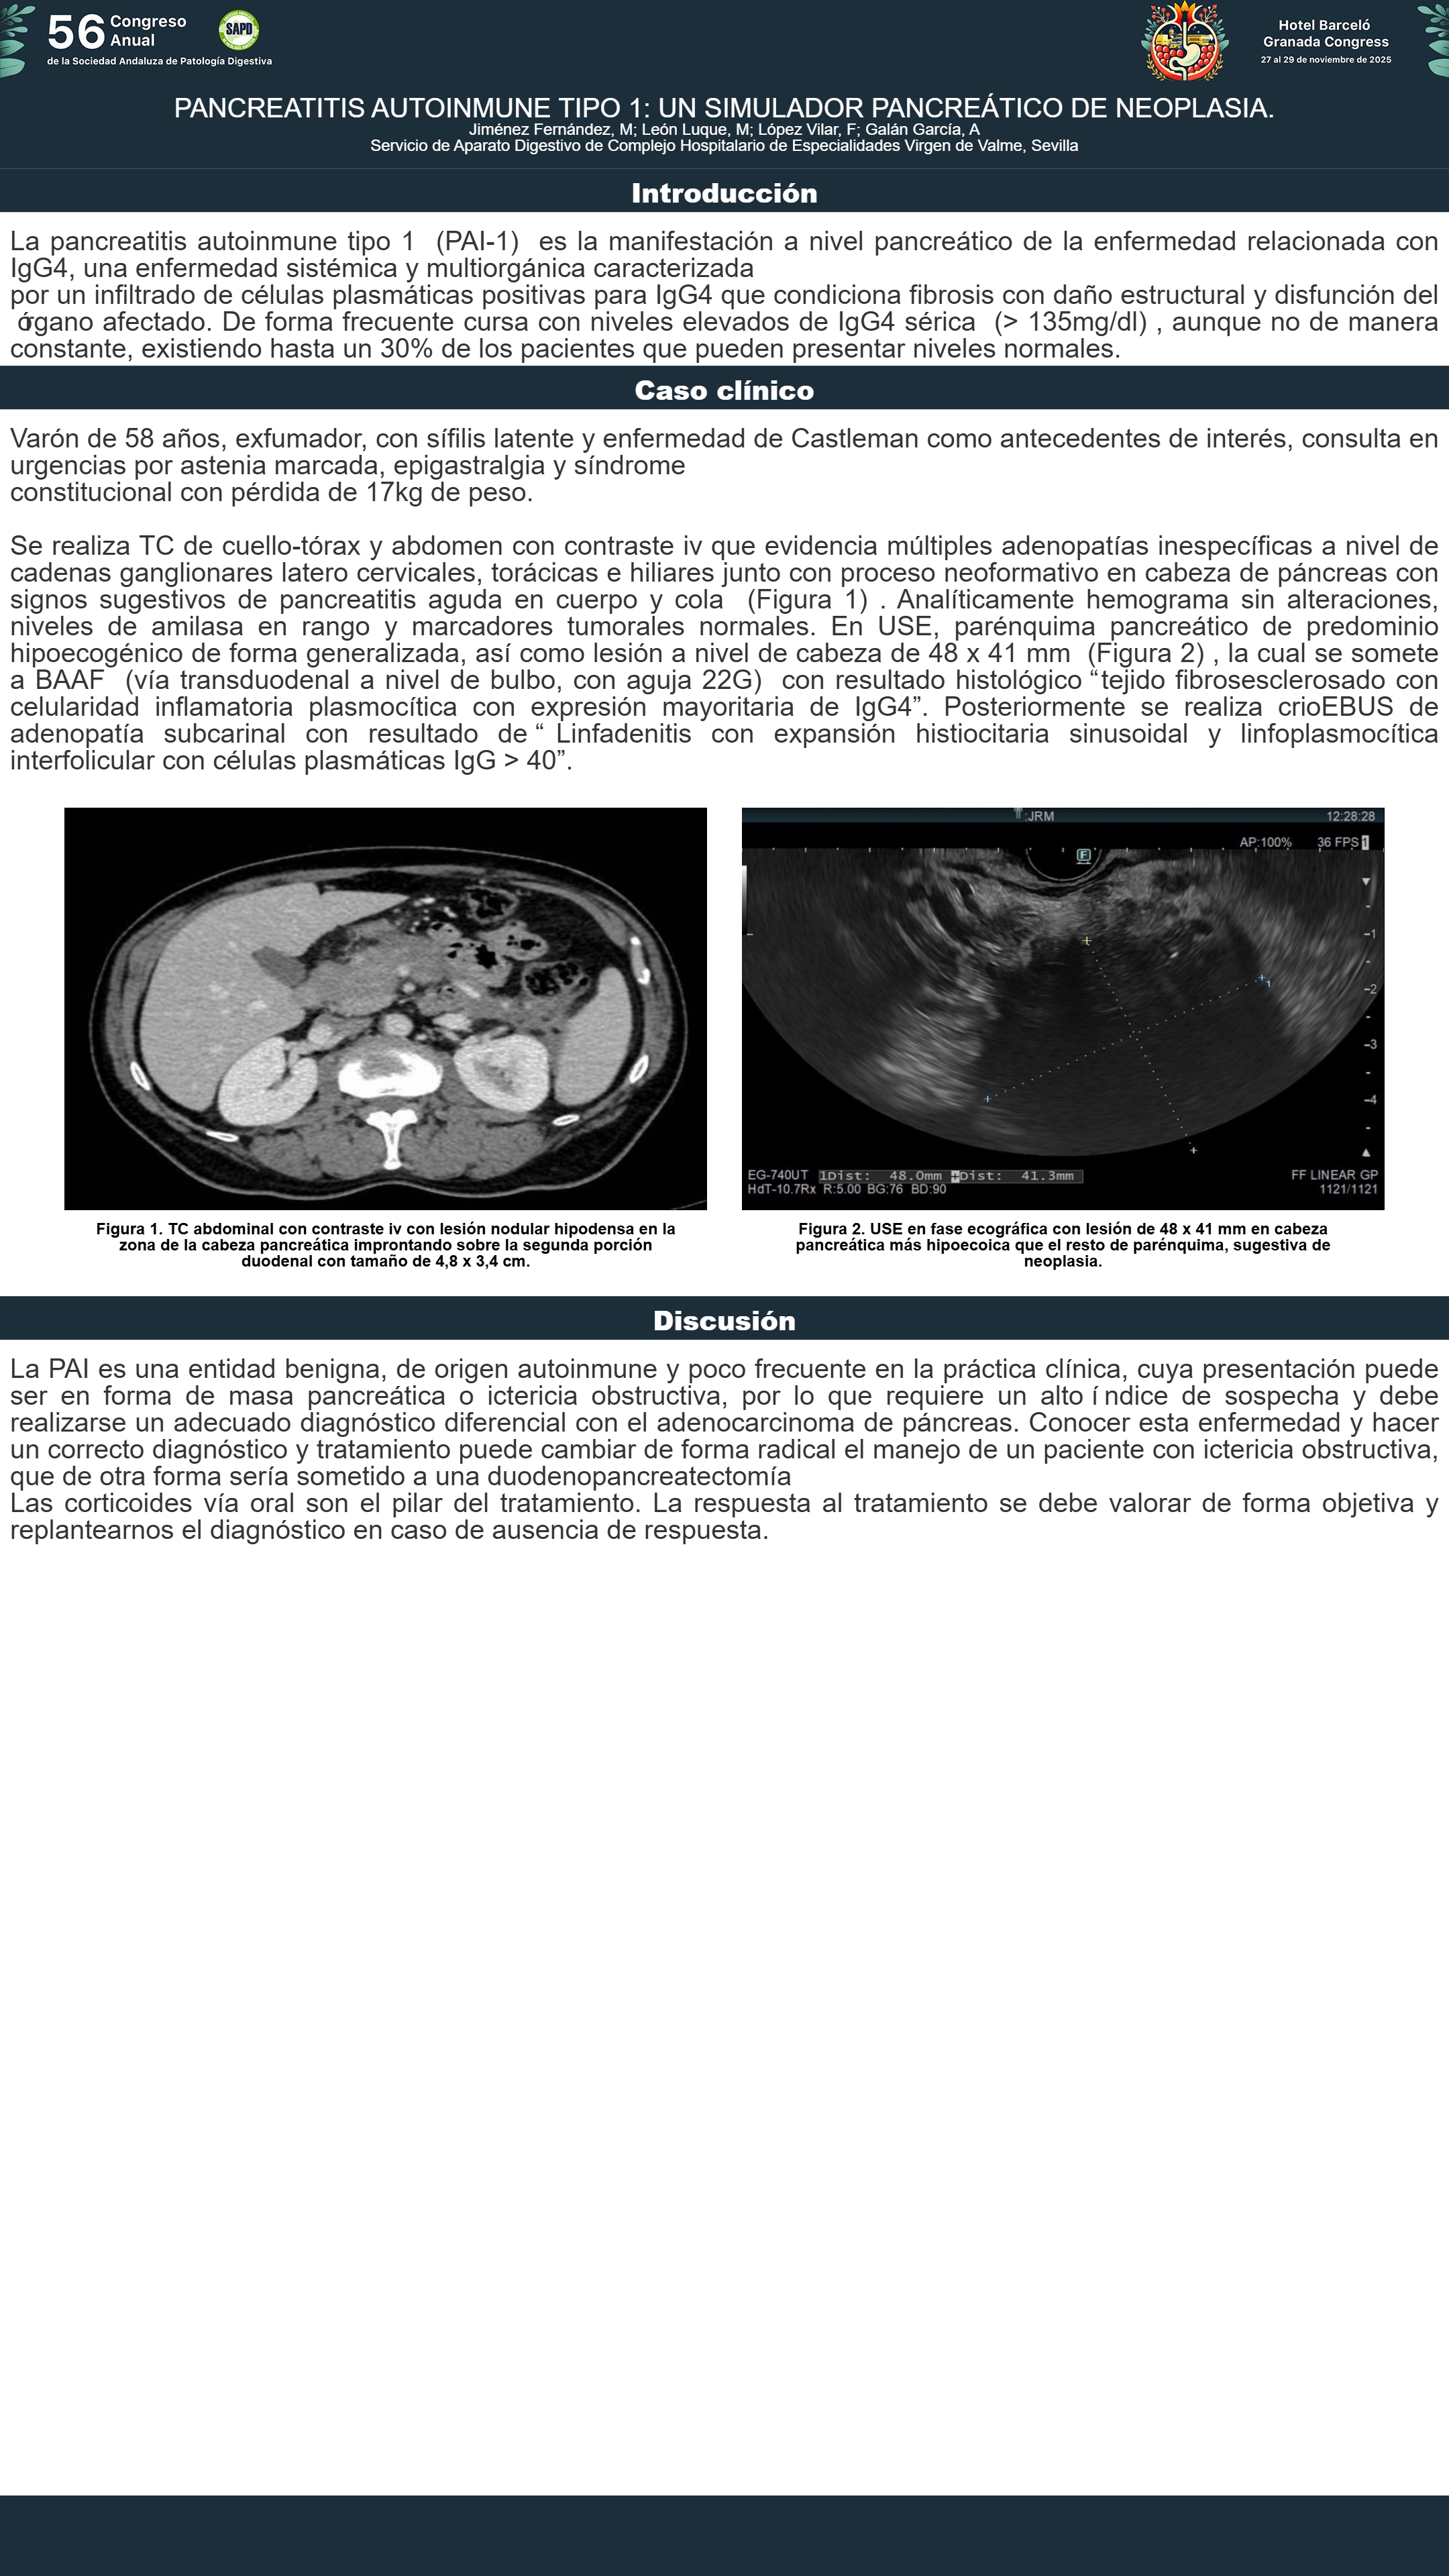

[CP-149] PANCREATITIS AUTOINMUNE TIPO 1: UN SIMULADOR PANCREÁTICO DE NEOPLASIA.